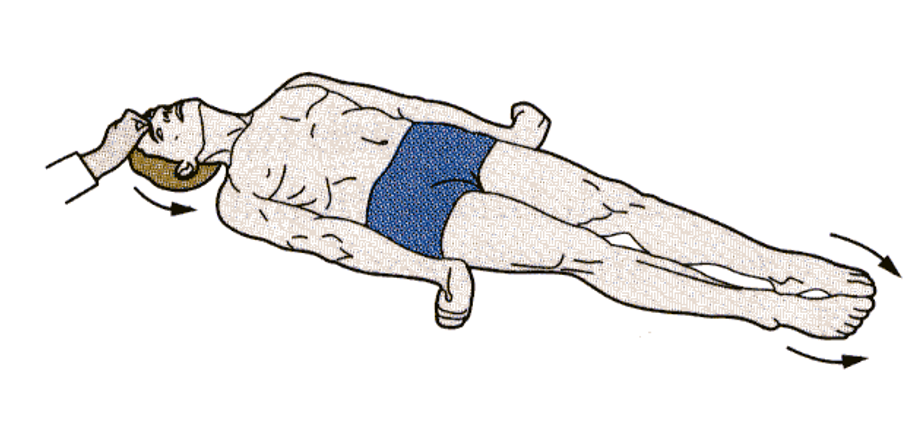

what posturing? which tracts are impaired?

decerebrate posturing. damage to cortex, rubrospinal (midbrain) lost, reticulo intact